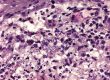

Am Ohrabstrich-Präparat waren zwischen den physiologisch vorhandenen Hornschollen reichlich Bakterien (Kokken) und auch vermehrt Malassezien zu sehen (Abb. 1). Neben reichlichen Chromatinfäden waren stellenweise auch einige intakte neutrophile Granulozyten vorhanden.

Abb. 1: Ohrabstrich-Präparat: Hornschollen, Chromatinfäden (vermutlich von Neutrophilen) sowie reichlich Kokken und einige Malassezien

Bildquelle: Dr. Maria Christian